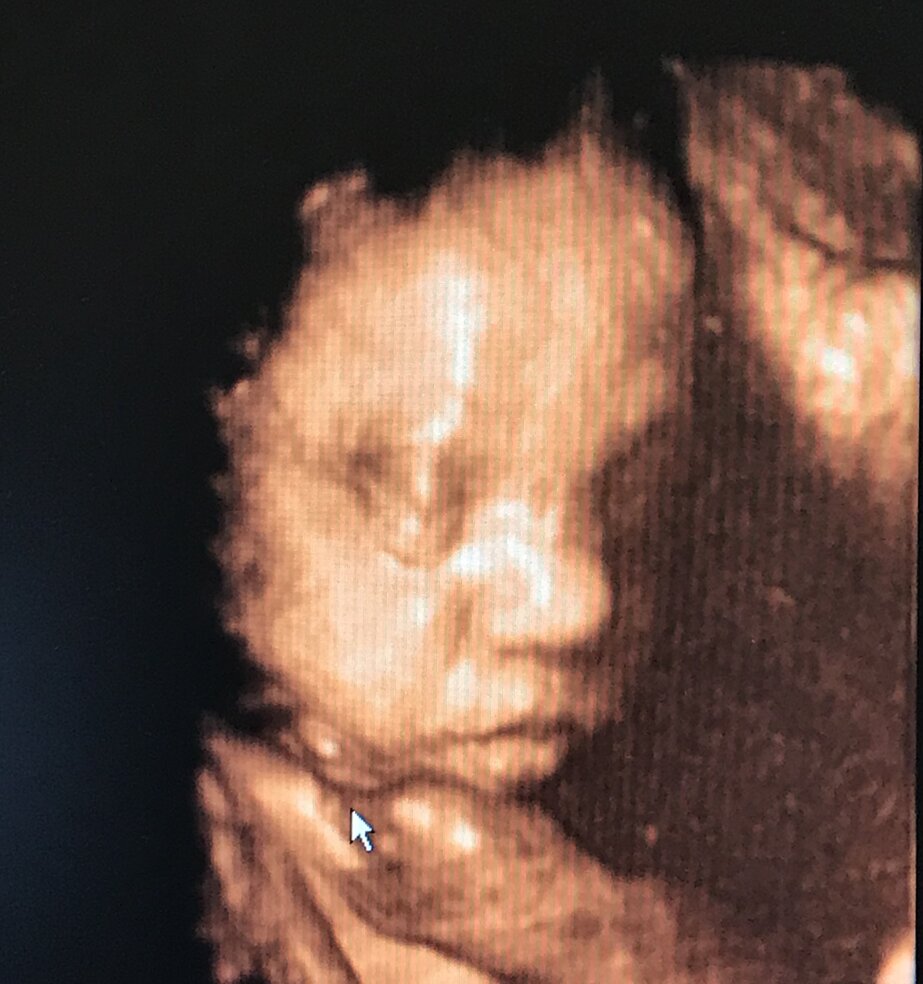

ECOGRAFIA 3D 4D